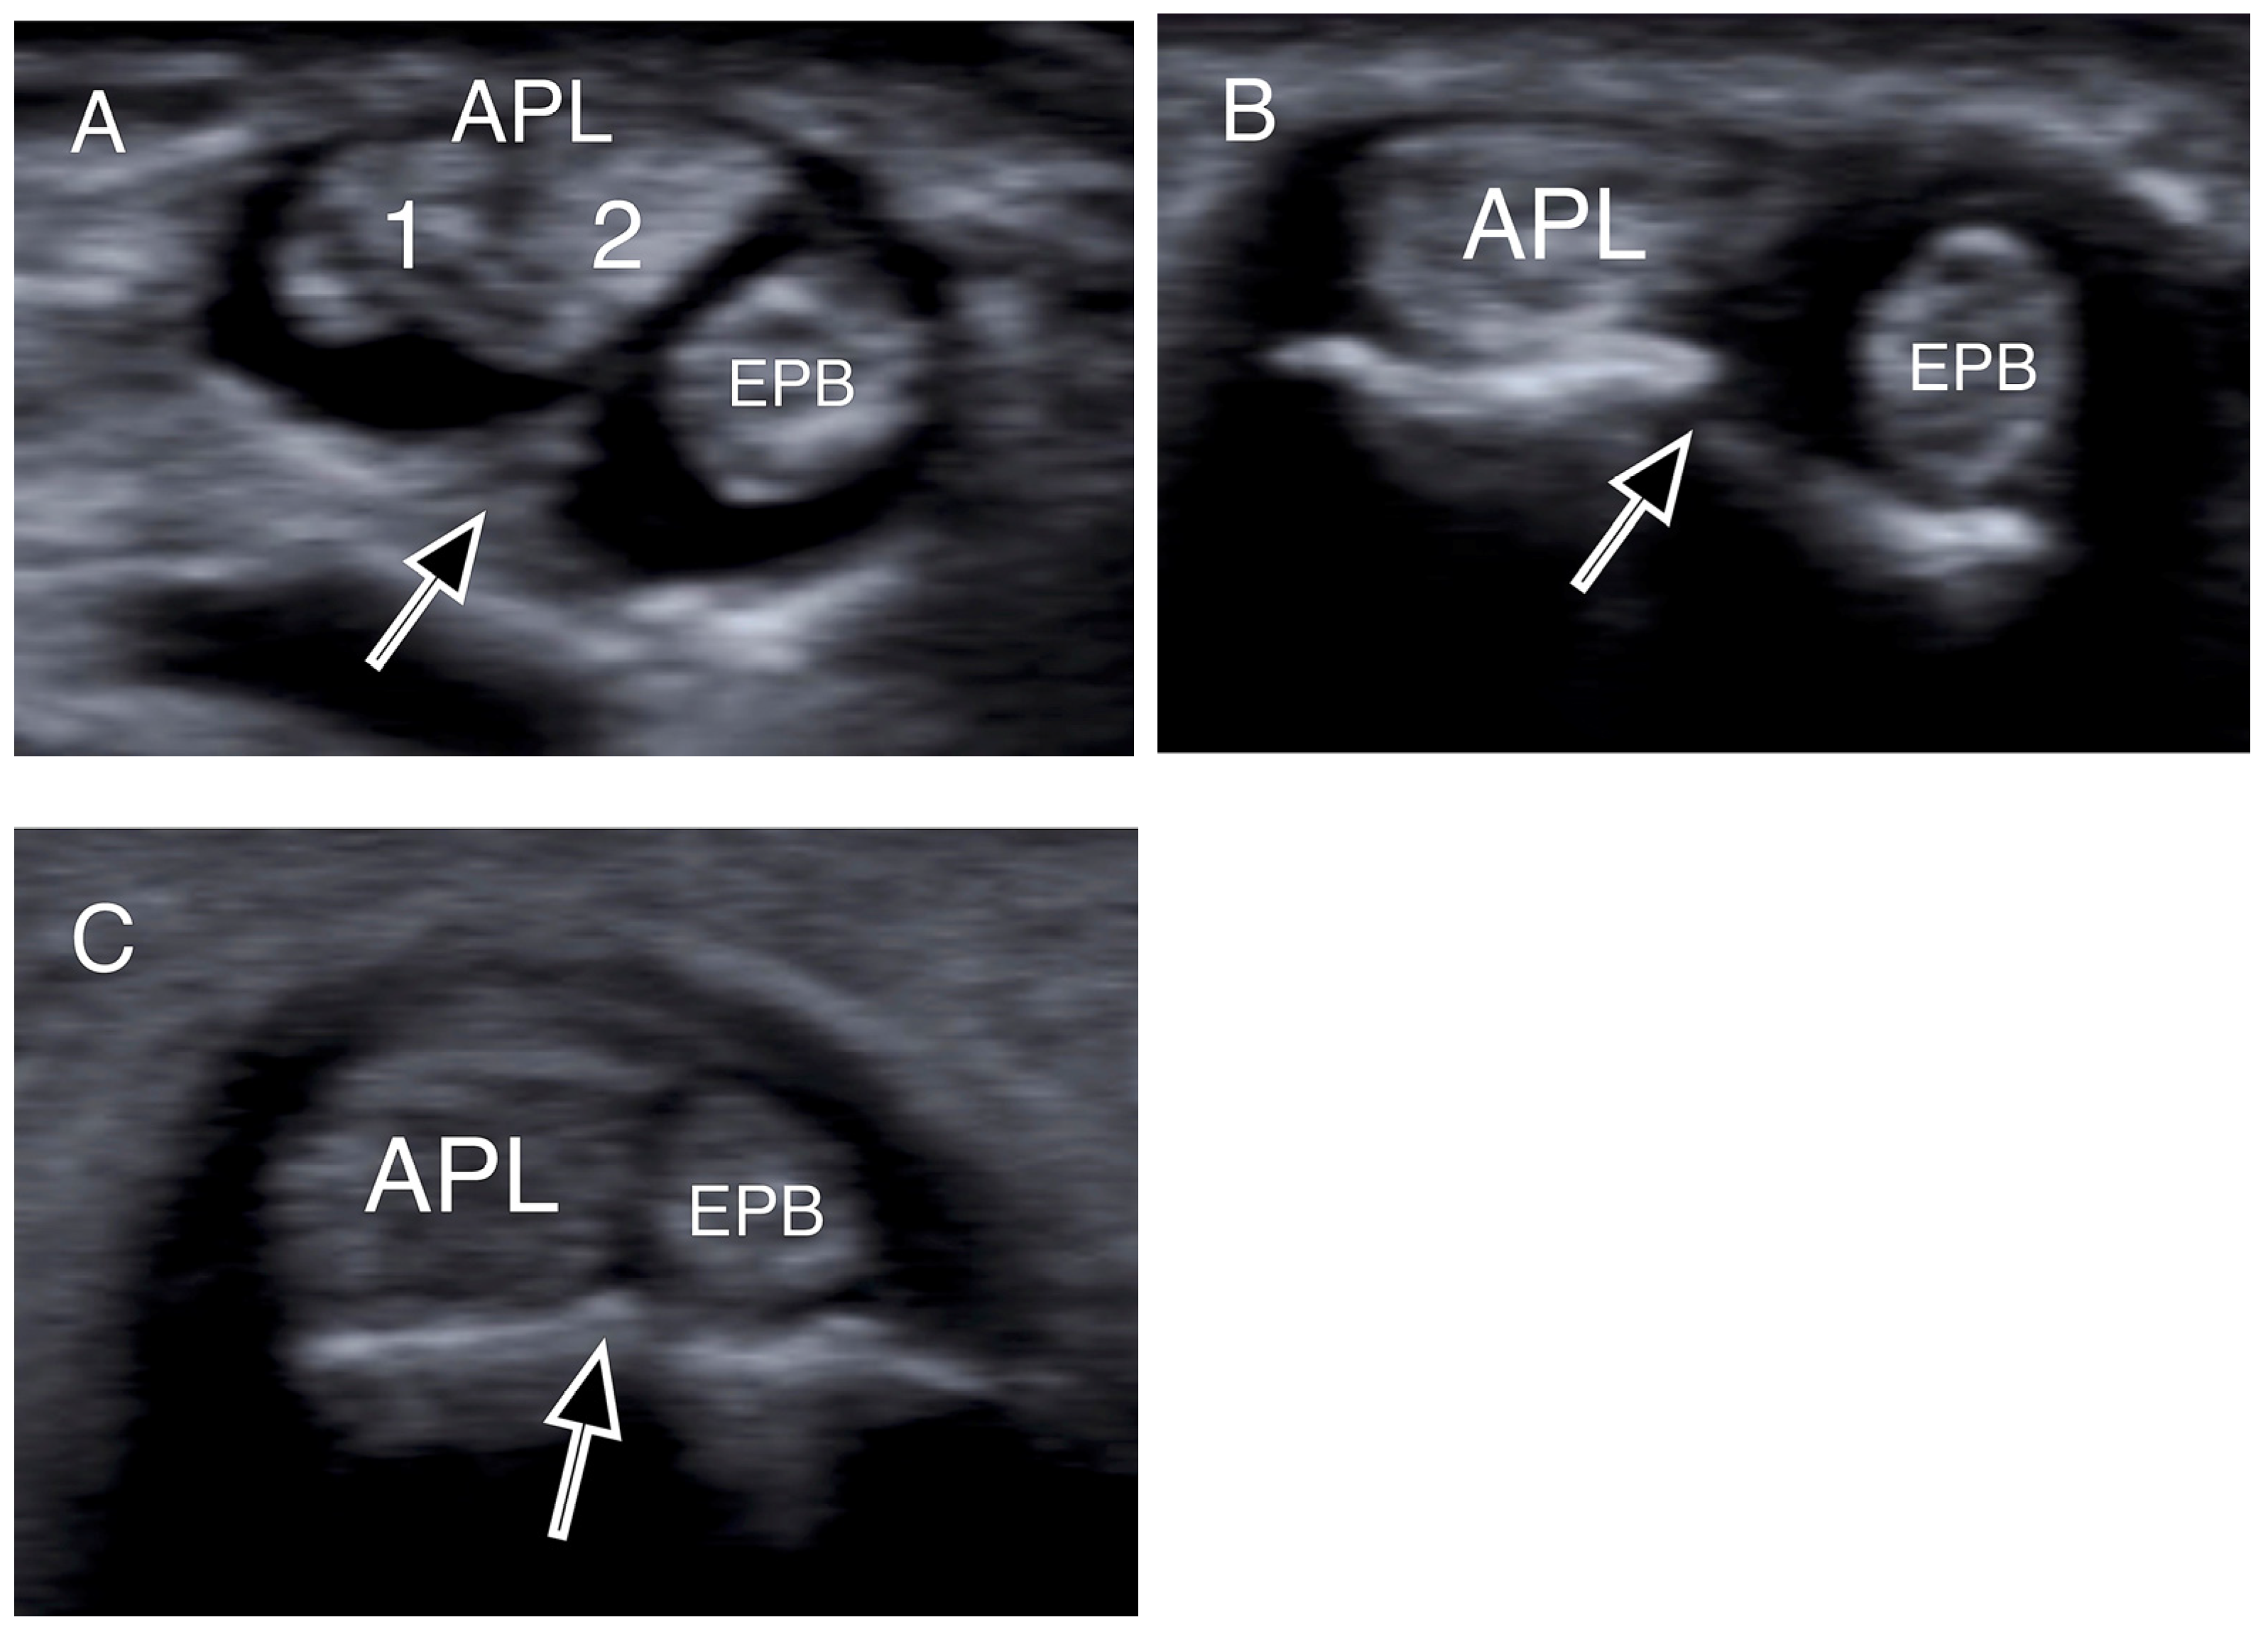

- Choi, S.J.; Ahn, J.H.; Lee, Y.J.; Ryu, D.S.; Lee, J.H.; Jung, S.M.; Park, M.S.; Lee, K.W. De Quervain Disease: US Identification of Anatomic Variations in the First Extensor Compartment with an Emphasis on Subcompartmentalization. Radiology 2011, 260, 480–486. [Google Scholar] [CrossRef]

- Kwon, B.C.; Choi, S.J.; Koh, S.H.; Shin, D.J.; Baek, G.H. Sonographic Identification of the Intracompartmental Septum in de Quervain’s Disease. Clin. Orthop. Relat. Res. 2010, 468, 2129–2134. [Google Scholar] [CrossRef]

| Intracompartmental septum | 27 (54%) |

| Double groove | 12 (24%) |